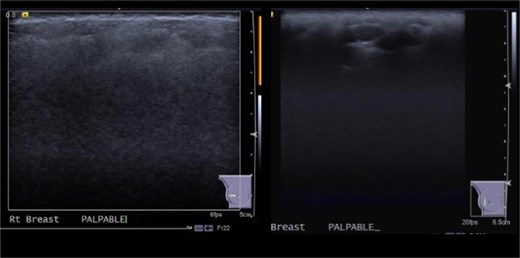

This was a 49-year-old lady of Philippine descent with previous free silicone injections in bilateral breasts in 1996. She was seen in the breast surgery clinic in October 2015 for a right breast lump in the upper outer quadrant. Mammogram showed extremely dense bilateral breasts with multiple dense oval opacities compatible with free silicone (Fig. 1). Ultrasound revealed a snowstorm appearance, with round cystic lesions scattered throughout both breasts representing silicone granuloma (Fig. 2). She was reassured at the time.

October 2015: Ultrasonography showing snowstorm appearance secondary to free silicone injection, with round cystic lesions scattered throughout both breasts representing silicone granuloma.